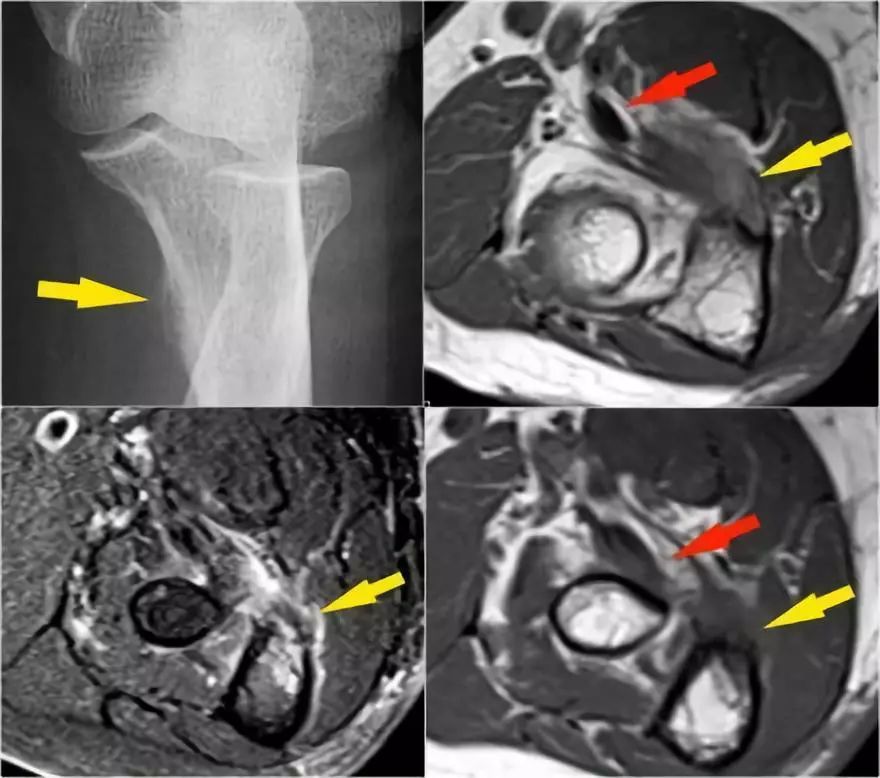

外翻过度综合征的关节病由于外翻过载,在肱骨-尺骨关节的后内侧部分存在剪切力。注意在T1W图像上看到的软骨下硬化(红色箭头)。在T2W图像上存在软骨下骨髓水肿和软骨损失(黄色箭头)。

下图是20岁棒球投手的图像。

冠状图像上有一个美丽的UCL前束,但注意到关节内侧部分有骨赘形成(红色箭头)。当我们按照顺序向下看,可以看到存在一小部分低信号强度(黄色箭头),这是UCL的一部分撕裂。

这是在X线片可以更好地观察(黄箭头 )。

当我们看轴向扫描时,我们可以欣赏巨大的骨赘形成。请注意,尺骨神经(蓝色箭头)紧邻这些骨赘,这些可能指示尺神经出现病变。